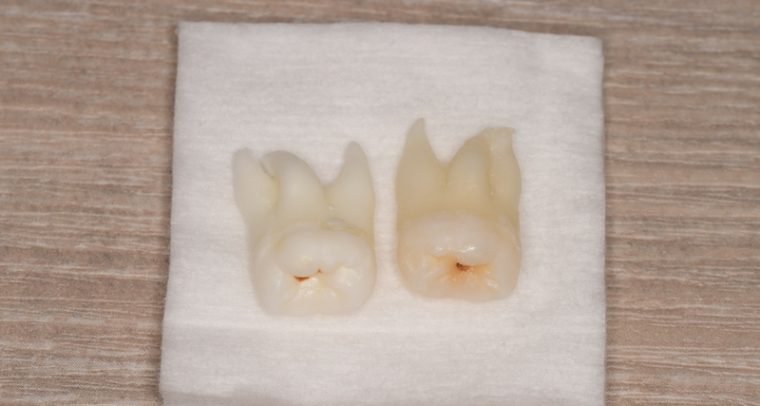

CASE 1

| 親知らずのはえ方 | 完全に出ていてまっすぐはえている |

| 抜歯期間 | 15分 |

| 抜歯費用 | 約2,000円(保険内) |

| 抜歯内容 |

何度か虫歯になり痛みはないが早めに抜きたい。 完全に頭が出ているため歯ぐきを切ったり骨を削らずに抜歯しました。 根の形も単純なため抜歯自体は5分もかからず上下ともに終わりました。 術後痛みや腫れも出ていません。 抜歯後は感染をしやすいため必ず抗生物質を飲み切ってください。 |